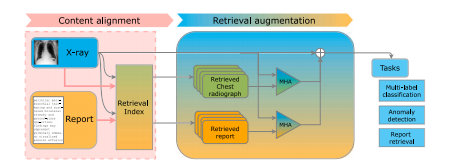

Fig. 15. Architecture overview of X-TRA.Source: From van Sonsbeek and Worring(2023)

图15:X-TRA的架构概述。来源: 出自范·松斯贝克和沃林(2023年)的研究